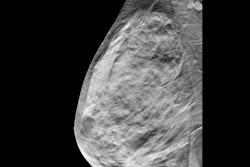

Imaging surveillance can be an alternative for managing architectural distortion on digital breast tomosynthesis (DBT) showing radial scarring without atypia, according to research published February 2 in the American Journal of Roentgenology.

Researchers led by Dr. Juan Villa Camacho from Massachusetts General Hospital n Boston found that such distortion on DBT with concordant nonmalignant pathology at biopsy has an overall upgrade rate to malignancy at surgery of 10.2%.

They also found that architectural distortion without atypia has a low upgrade rate of 2.2%, and 28.2% with atypia.